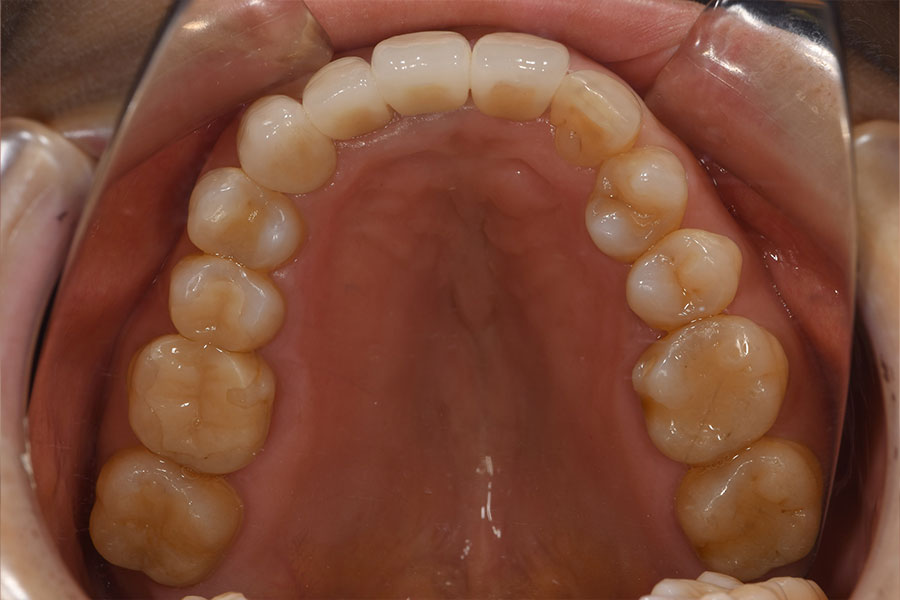

After -上顎-